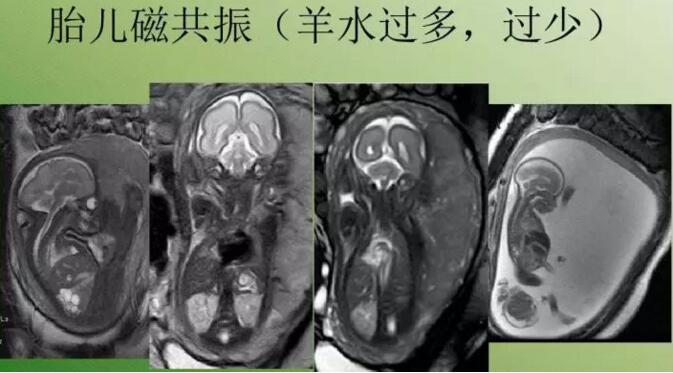

磁共振可解決羊水太少超聲不好顯示的問題

磁共振檢查不受胎兒骨骼及羊水量的影響,對胎兒中樞神經(jīng)系統(tǒng)、羊水過少、雙胎、孕周較大時顯示很好,特別是孕晚期胎頭入盆或胎兒顱骨骨化時。

磁共振圖像可以在各個方位看到寶寶的顱腦,還能看到寶寶撅起的小嘴。

磁共振圖像可以在各個方位看到寶寶的顱腦